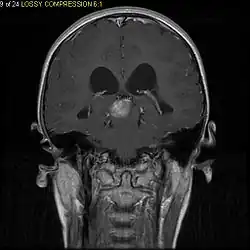

T1-weighted coronal MRI image postcontrast showing heterogeneous contrast enhancement within the presumed tectal plate glioma